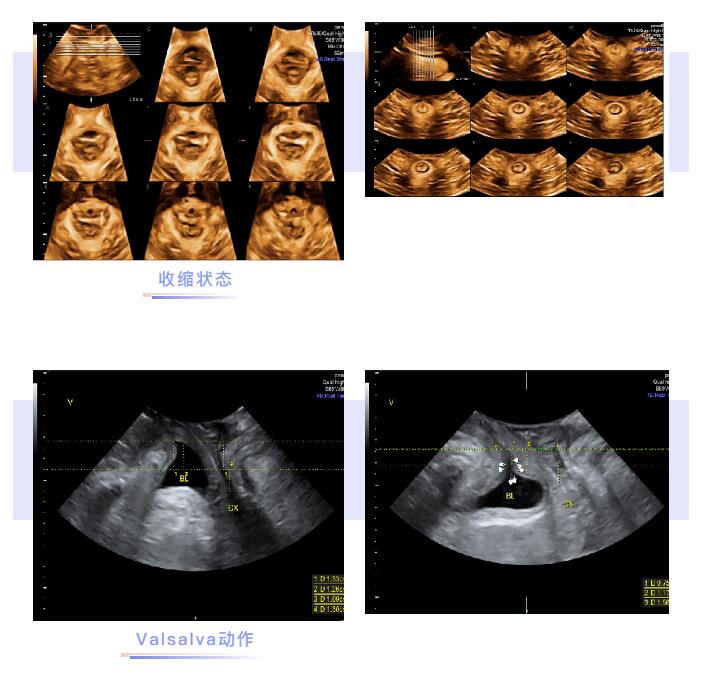

盆底超声就是应用超声探头经会阴来观察比较女性静息,缩肛,Valsalva状态盆腔器官的变化,评估盆腔器官下移程度及盆腔肌肉组织损伤程度。

可以实时动态观察不同状态下盆底结构和功能的变化

可以直接观察盆腔脏器的结构和位置改变

可以获得盆底完整的声像图